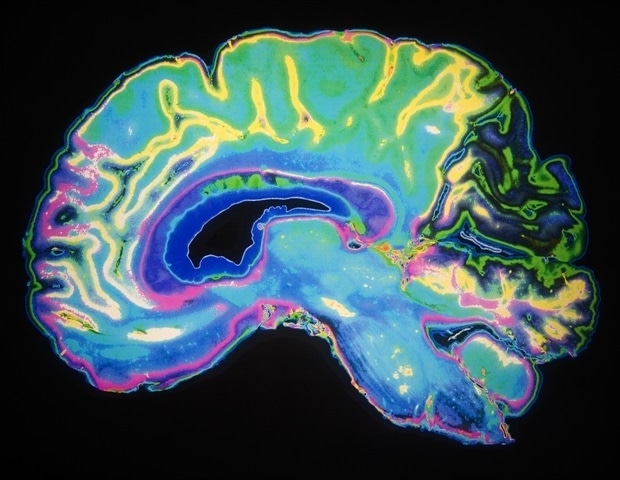

“We sometimes detect meningiomas in older people as incidental findings on MRI scans when looking for other things. They are often benign, in most cases causing absolutely no problems and growing very slowly. Malignant variants are found but very rarely,”

This research provides further evidence that meningiomas predominantly affect older women. According to Erik Thurin, the lead investigator of the study, the prevalence among women is noteworthy. “Meningiomas primarily affect older women. Among women, there was a 2.7 percent risk of a tumor, five times higher than for men,” Thurin states.

The study was executed in collaboration with Professor Ingmar Skoog’s research team, utilizing data from the extensive H70 population study, which invited a cohort of 70-year-olds for examinations including MRI scans of the brain. Researchers aimed to explore suspicions regarding the underdiagnosis of meningiomas in senior populations, a concern raised in studies from other countries.